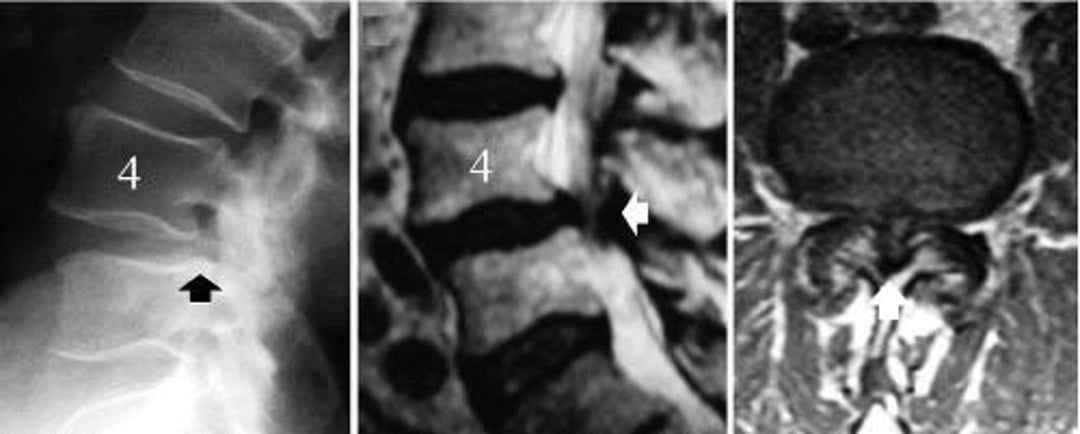

Sténose rachidienne lombaire causée par un spondylolisthésis dégénératif de L4-L5

L'image de gauche est une radiographie de profil du rachis lombaire montrant un glissement de la vertèbre L4 (flèche noire, le bord postérieur du corps vertébral L5 ne s'aligne pas avec celui de L4). L'image du milieu est une IRM mésagittale montrant la compression des structures neurales (flèche blanche). L'image de droite est une IRM axiale montrant une sténose spinale sévère au niveau du spondylolisthésis dégénératif, L4-5 (flèche blanche).